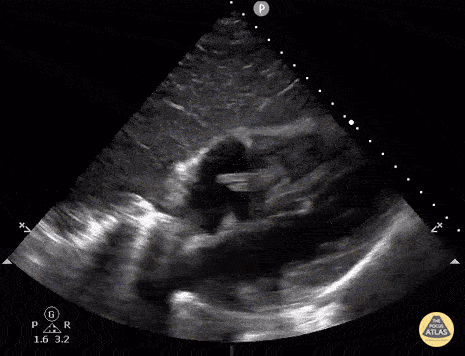

Recurrent fevers and this on PLAX:

Mitral valve Endocarditis